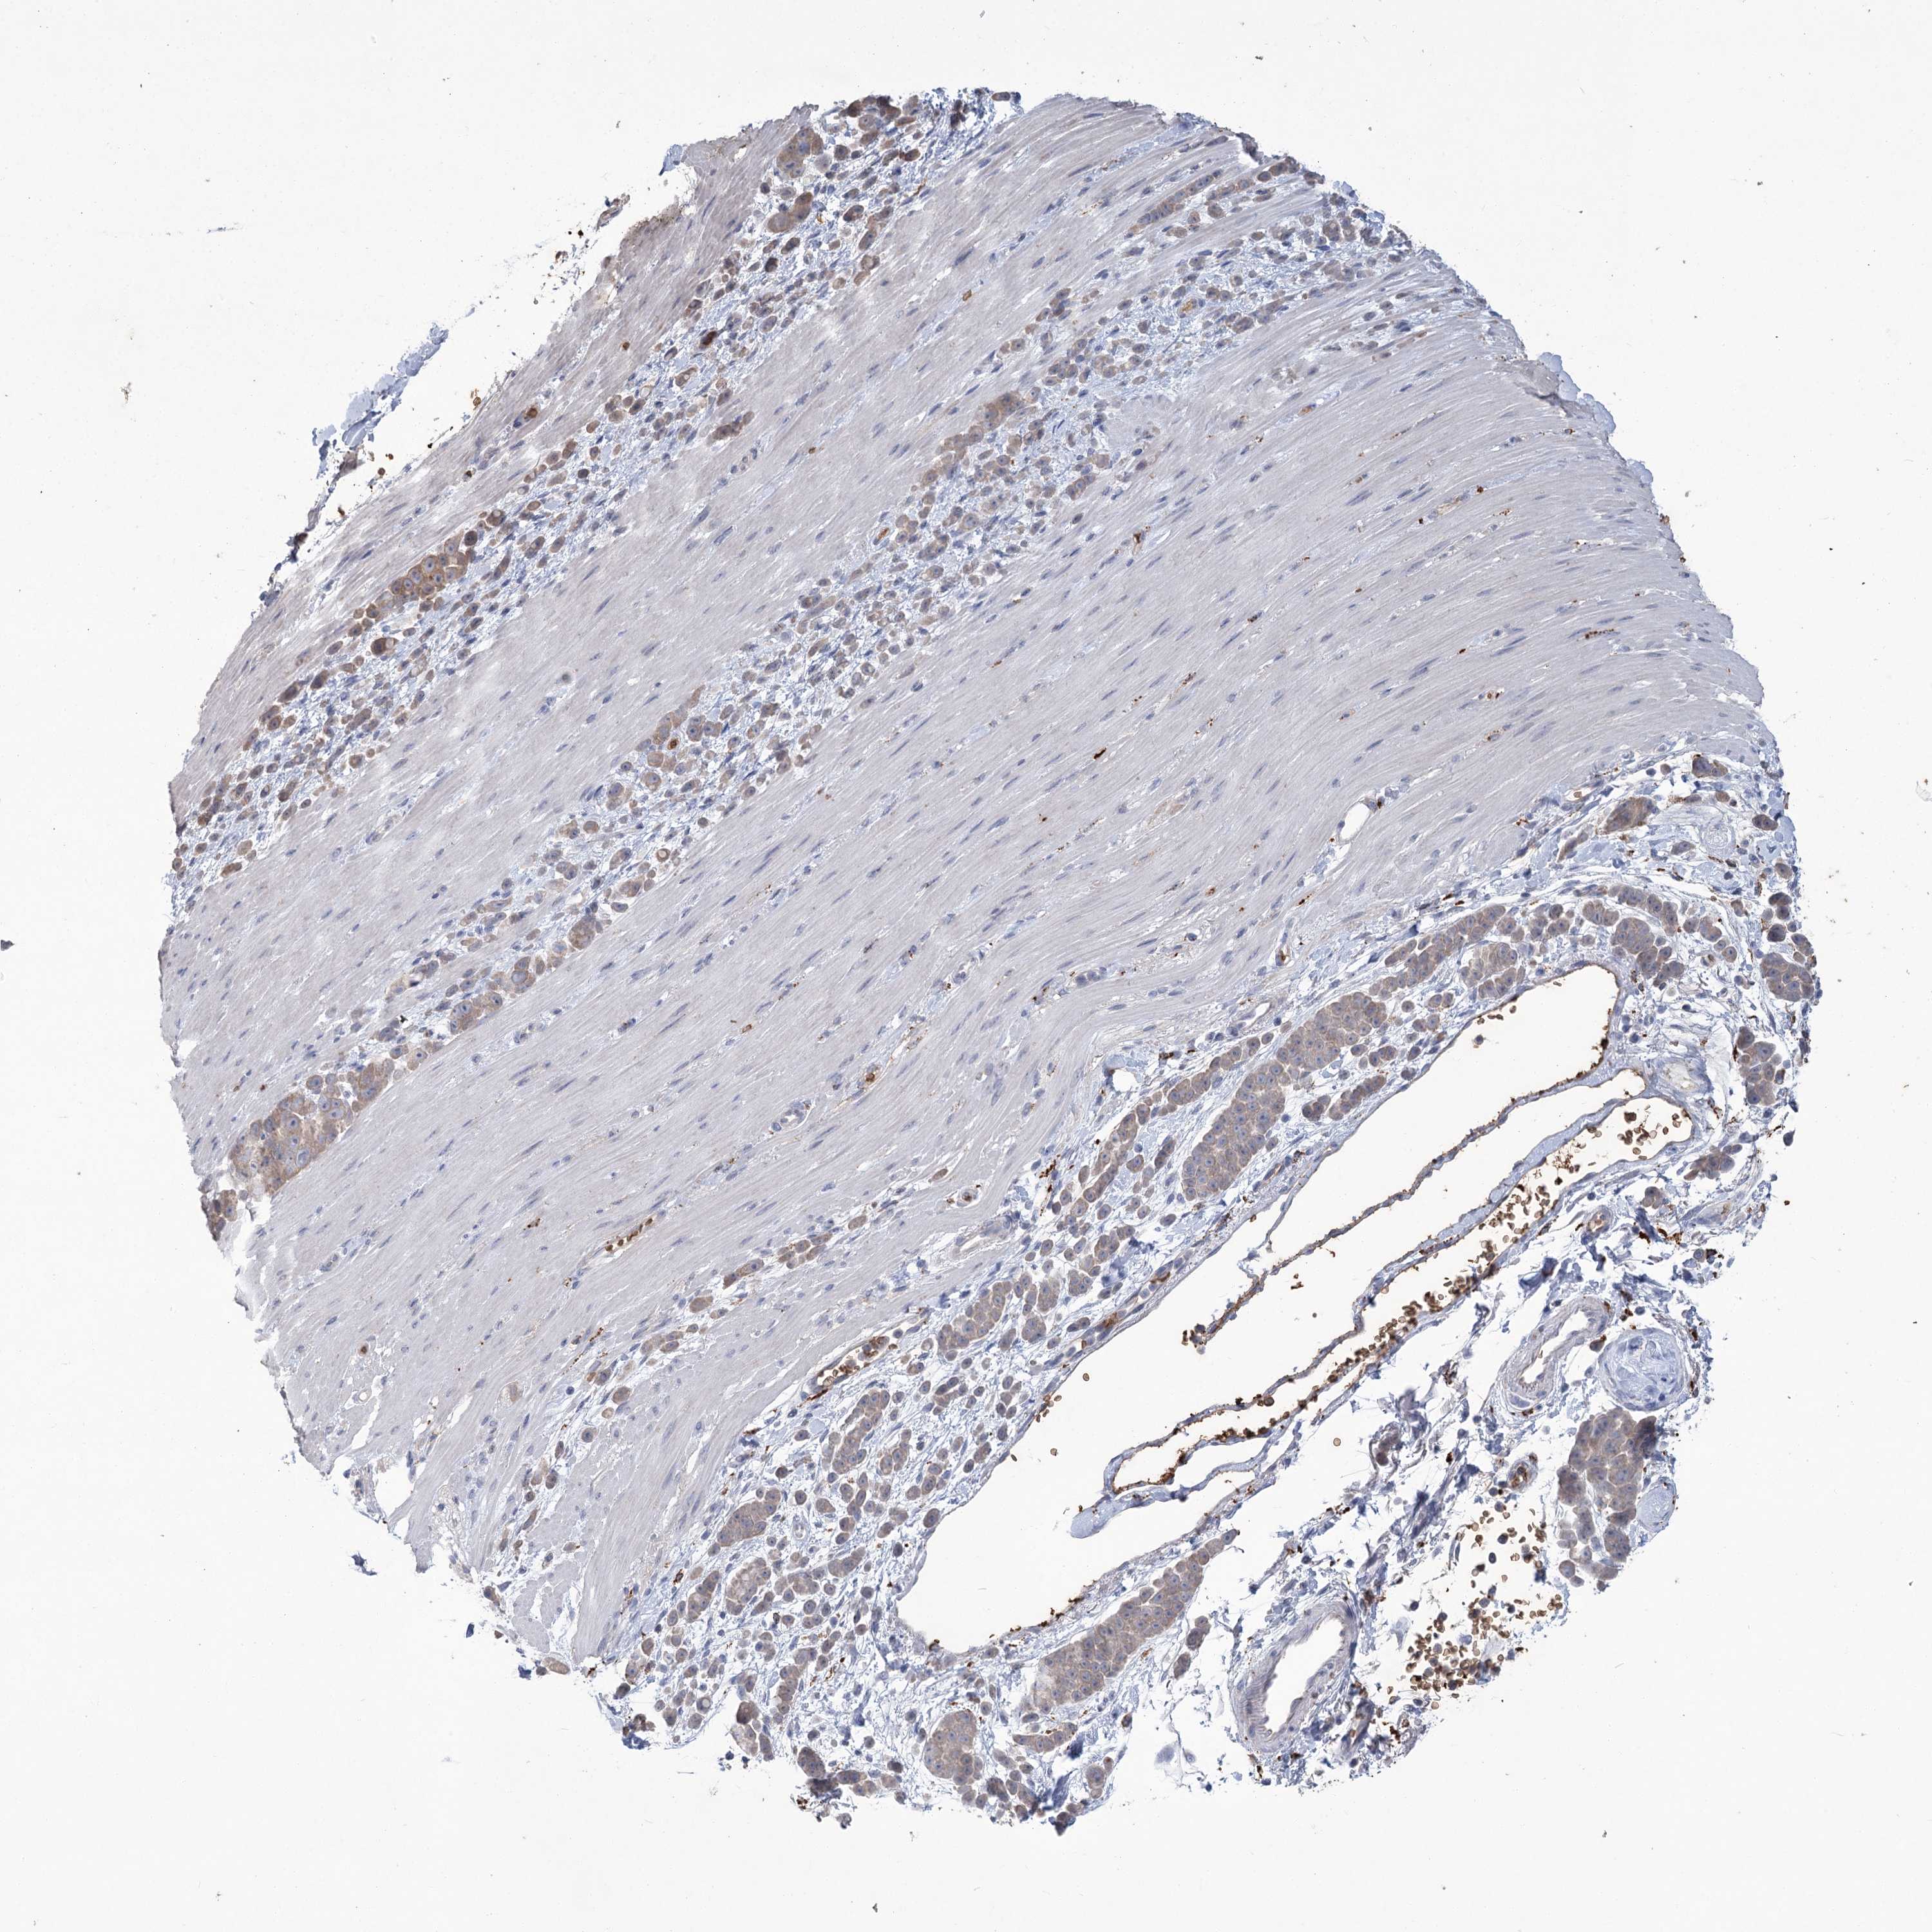

PANCREATIC CANCER - Protein expressioni

A mouse-over function shows sample information and annotation data. Click on an image to view it in a full screen mode. Samples can be filtered based on level of antibody staining by selecting one or several of the following categories: high, medium, low and not detected. The assay and annotation is described here.

Note that samples used for immunohistochemistry by the Human Protein Atlas do not correspond to samples in the TCGA dataset.

Antibody stainingi

Antibody staining in the annotated cell types in the current human tissue is reported as not detected, low, medium, or high, based on conventional immunohistochemistry profiling in selected tissues. This score is based on the combination of the staining intensity and fraction of stained cells.

Each image is clickable and will lead to virtual microscopy that enables deeper exploration of all samples and also displays staining intensity scores, fraction scores and subcellular localization as well as patient and tissue information for each sample.

Antibody HPA043780

Antibody CAB032534

Adenocarcinoma, NOS